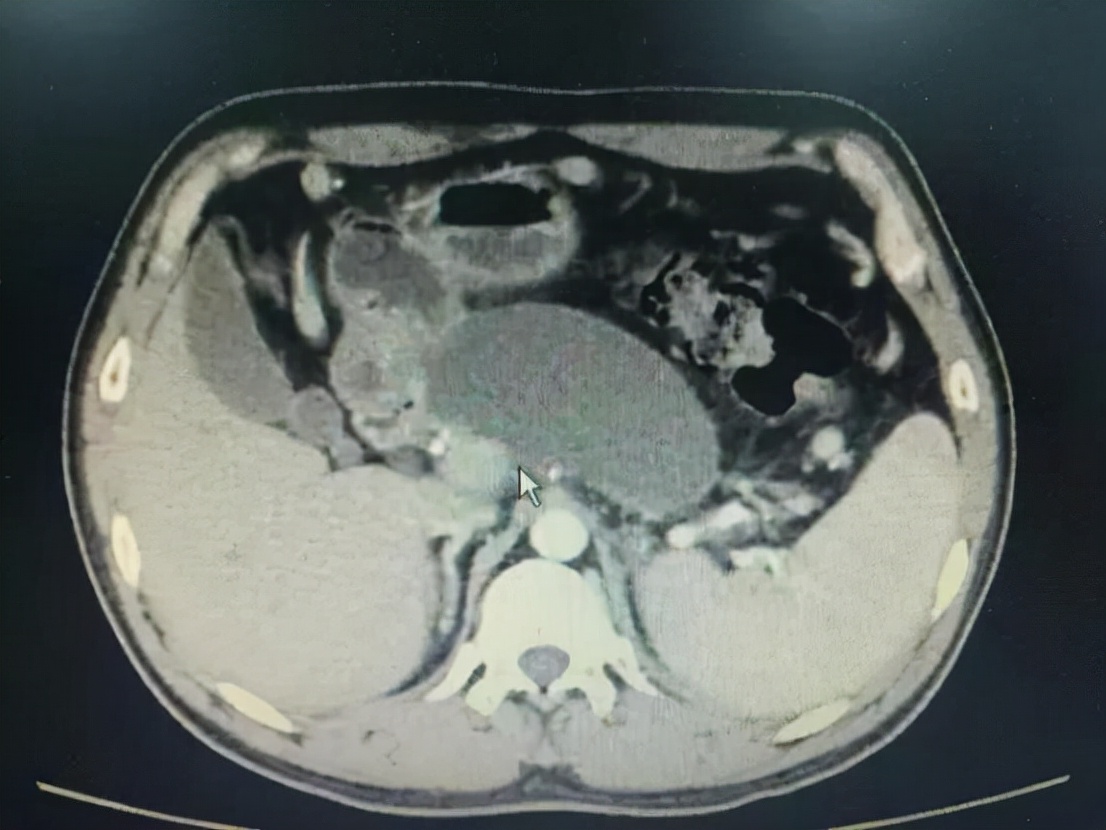

前面都说了肝囊肿很常见,为什么肝囊肿还需要引起警惕呢?因为,肝囊肿中有一个很特别的囊肿,需要高度警惕:寄生虫性肝囊肿。

所谓寄生虫性肝囊肿,即是因为寄生虫侵犯了肠道,在其内部产卵筑巢。而幼小的卵虫会顺着血管进入到肝脏内,诱发肝脏囊肿。因此也称之为肝包虫病。

肝脏囊肿

由于寄生虫性肝囊肿多会产生较多的刺激性物质,容易对肝脏的功能产生影响,因此如果发现确诊了肝包虫病,且伴有肝功能的异常,应及时有效的对症处理。

当然,非寄生虫性肝囊肿如果直径超过了10厘米,会引起局部压迫性的症状,则应该手术治疗。